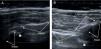

El método de evaluación de las sacroilíacas es simple. Se coloca al paciente en decúbito prono y la sonda en el plano transversal; la exploración empieza en posición ligeramente cefálica al primer agujero sacro, donde comienza la articulación sacroilíaca, y se desplaza en sentido caudal hasta sobrepasar el segundo agujero sacro, donde acaba la sacroilíaca. En esta posición se visualiza la región dorsal de la articulación sacroilíaca en toda su extensión. Como marcas óseas de interés observamos, la espina sacra, la cortical del sacro, la articulación sacroilíaca y el ilíaco. En los cortes cefálicos el hueso ilíaco aparece superficial a la cortical sacra, mientras que en los cortes caudales la cortical del ilíaco aparece más profunda que los contornos sacros. Conviene identificar los agujeros sacros primero y segundo, ya que tienen vasos fisiológicos, en los que se detecta señal Doppler y no debe confundirnos con el Doppler articular o entésico de las articulaciones sacroilíacas. También se visualizan los ligamentos iliolumbares y sacroilíacos. El conocimiento de todas estas estructuras es básico para poder realizar una correcta exploración de la articulación sacroilíaca (fig. 3).

Ecografía de las articulaciones sacroilíacas. A) Corte transversal, región caudal distal al segundo agujero sacro, señal Doppler ausente. B) Corte transversal, porción cefálica próxima al primer agujero sacro, señal Doppler presente. Las flechas indican los contornos del hueso sacro e ilíaco, la cabeza de flecha señala la articulación.